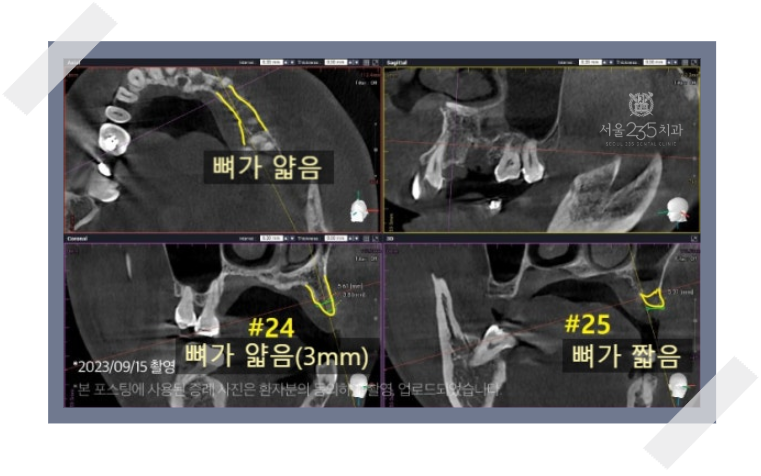

1. 잇몸뼈가 심각하게 부족한 경우

고난이도 임플란트의 가장 대표적인 사례는 임플란트를 심을 잇몸뼈(치조골)가

절대적으로 부족한 경우입니다.

그런데 왜 뼈가 부족해질까요?

왜냐하면 치아를 상실한 채 오래 방치하거나, 심한 잇몸 염증(치주염)을

앓으면 뼈가 점차 녹아내려 흡수됩니다.

CT촬영을 해보면 임플란트를 심기에는 뼈의 폭이

매우 얇거나 높이가 현저히 낮은 상태인 것을 확인할 수 있습니다.